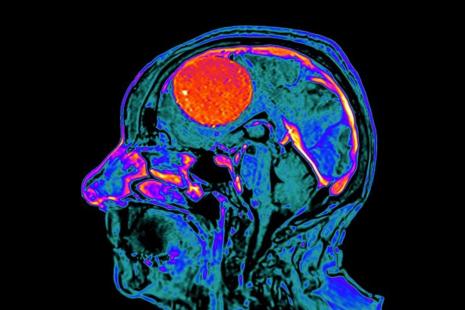

En France, depuis 2018, des mesures ont été mises en place pour réduire le risque de méningiome associé à l’utilisation de fortes doses (≥ 25 mg) d’acétate de cyprotérone (Androcur et génériques). Notamment, une attestation d’information cosignée du médecin et du patient doit être présentée avant toute délivrance, une surveillance par IRM cérébrale est mise en place…

Autre fait positif marquant : l’étude révèle une très forte diminution du nombre d’opérations de méningiomes associées à l’acétate de cyprotérone (-93 %), notamment chez les femmes (7 femmes opérées en 2021 contre 95 en 2017). Cette baisse est observée alors que le dépistage par IRM cérébrale a significativement progressé, avec plus de la moitié des personnes traitées qui ont réalisé cet examen en 2021, contre à peine 10 % en 2018.